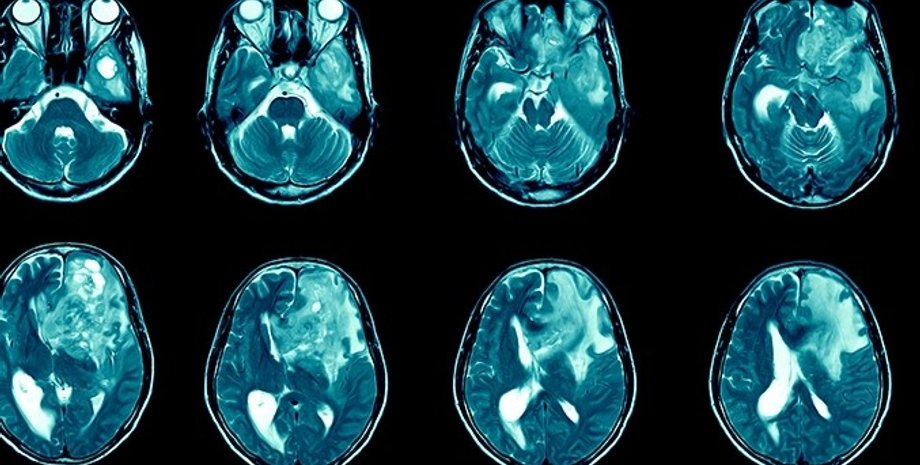

рак мозку, мозок, гліобластома

Гліобластома в головному мозку людини | Фото: Getty Images Plus

Гліобластома є однією з найпоширеніших і найагресивніших форм раку головного мозку. До того ж вона надзвичайно важко піддається лікуванню. На щастя, дослідники вважають, що їм, можливо, вдалося знайти спосіб боротьби з цим типом раку, пише Science Alert.